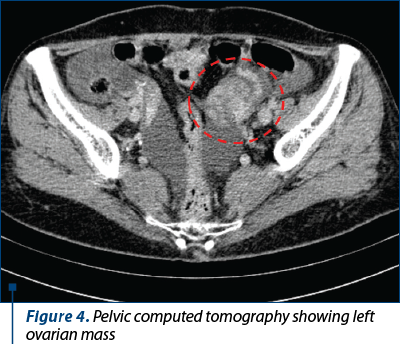

In June 2018, the patient presents with abdominal pain, postprandial bloating, nausea, vomiting and abdominal distension (ECOG 3). Contrast-enhanced chest-abdomen-pelvis CT showed stable pulmonary metastases and left ovarian mass (Figure 4).

The serum cancer antigen 125 (CA-125) level (65 U/mL) was higher than the normal range (1.9-16.3 U/mL). In July 2018, an exploratory laparotomy was performed, revealing chylous ascites and a 8x7 cm ovarian mass, followed by left adnexectomy.

Figure 4. Pelvic computed tomography showing left ovarian mass